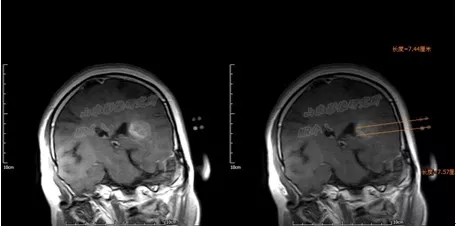

术后24小时内MRI/CT图像融合

MR/CT融合图像解决了I125放射性粒子在磁共振图像上显示不清、CT图像病灶轮廓勾画

困难的缺点,达到精准的病灶与粒子的空间分布显示,有利于术后的TPS验证。